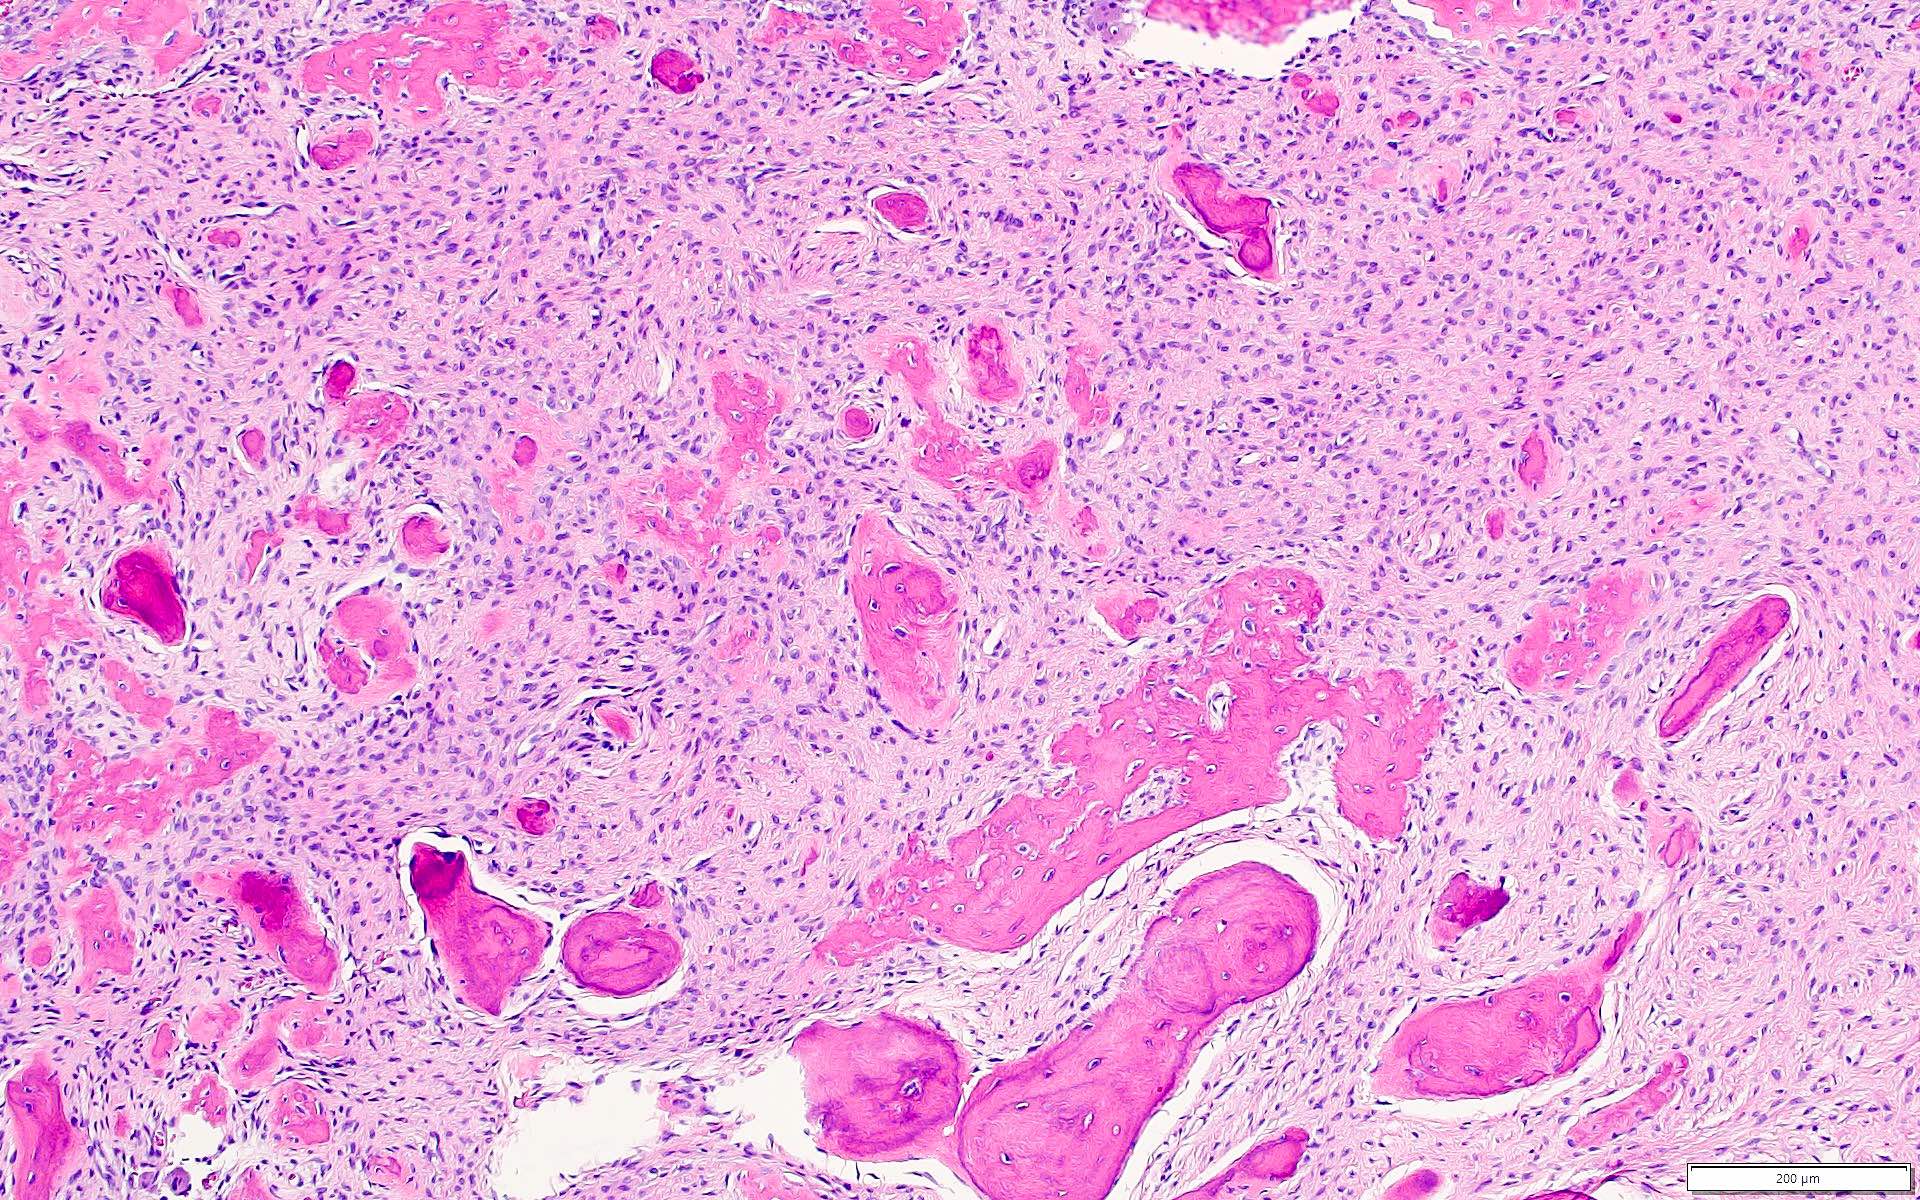

Microscopic (histologic) description

- Well defined lesion; may have thin fibrous capsule

- Well demarcated margin from surrounding normal bone

- Lesion consists of variable proportion of fibrous and mineralized tissue, more heavily mineralized centrally; it shows variation in the amount and type of mineralization, even within a single lesion

- Osteoblastic rimming of bone trabeculae is frequent (J Stomatol Oral Maxillofac Surg 2022;123:364)

- Stroma is fibroblastic with areas of hypercellularity and nuclear hyperchromasia

- No significant atypia and mitoses are infrequent (Head Neck Pathol 2020;14:70)

- Woven to lamellar bone, osteoid and dense acellular or paucicellular basophilic rounded cementum-like calcifications may all be present (Head Neck Pathol 2020;14:70)

- Bony trabeculae may form thick anastomosing strands or fuse into large sheets centrally

- Areas resembling cemento-ossifying fibroma may be seen in psammomatoid and trabecular ossifying fibroma; cemento-ossifying fibroma may contain ossicles like psammomatoid ossifying fibroma

Microscopic (histologic) images

Contributed by Saira Javeed, M.B.B.S., M.Phil., Kelly Magliocca, D.D.S., M.P.H. and Molly Housley Smith, D.M.D.